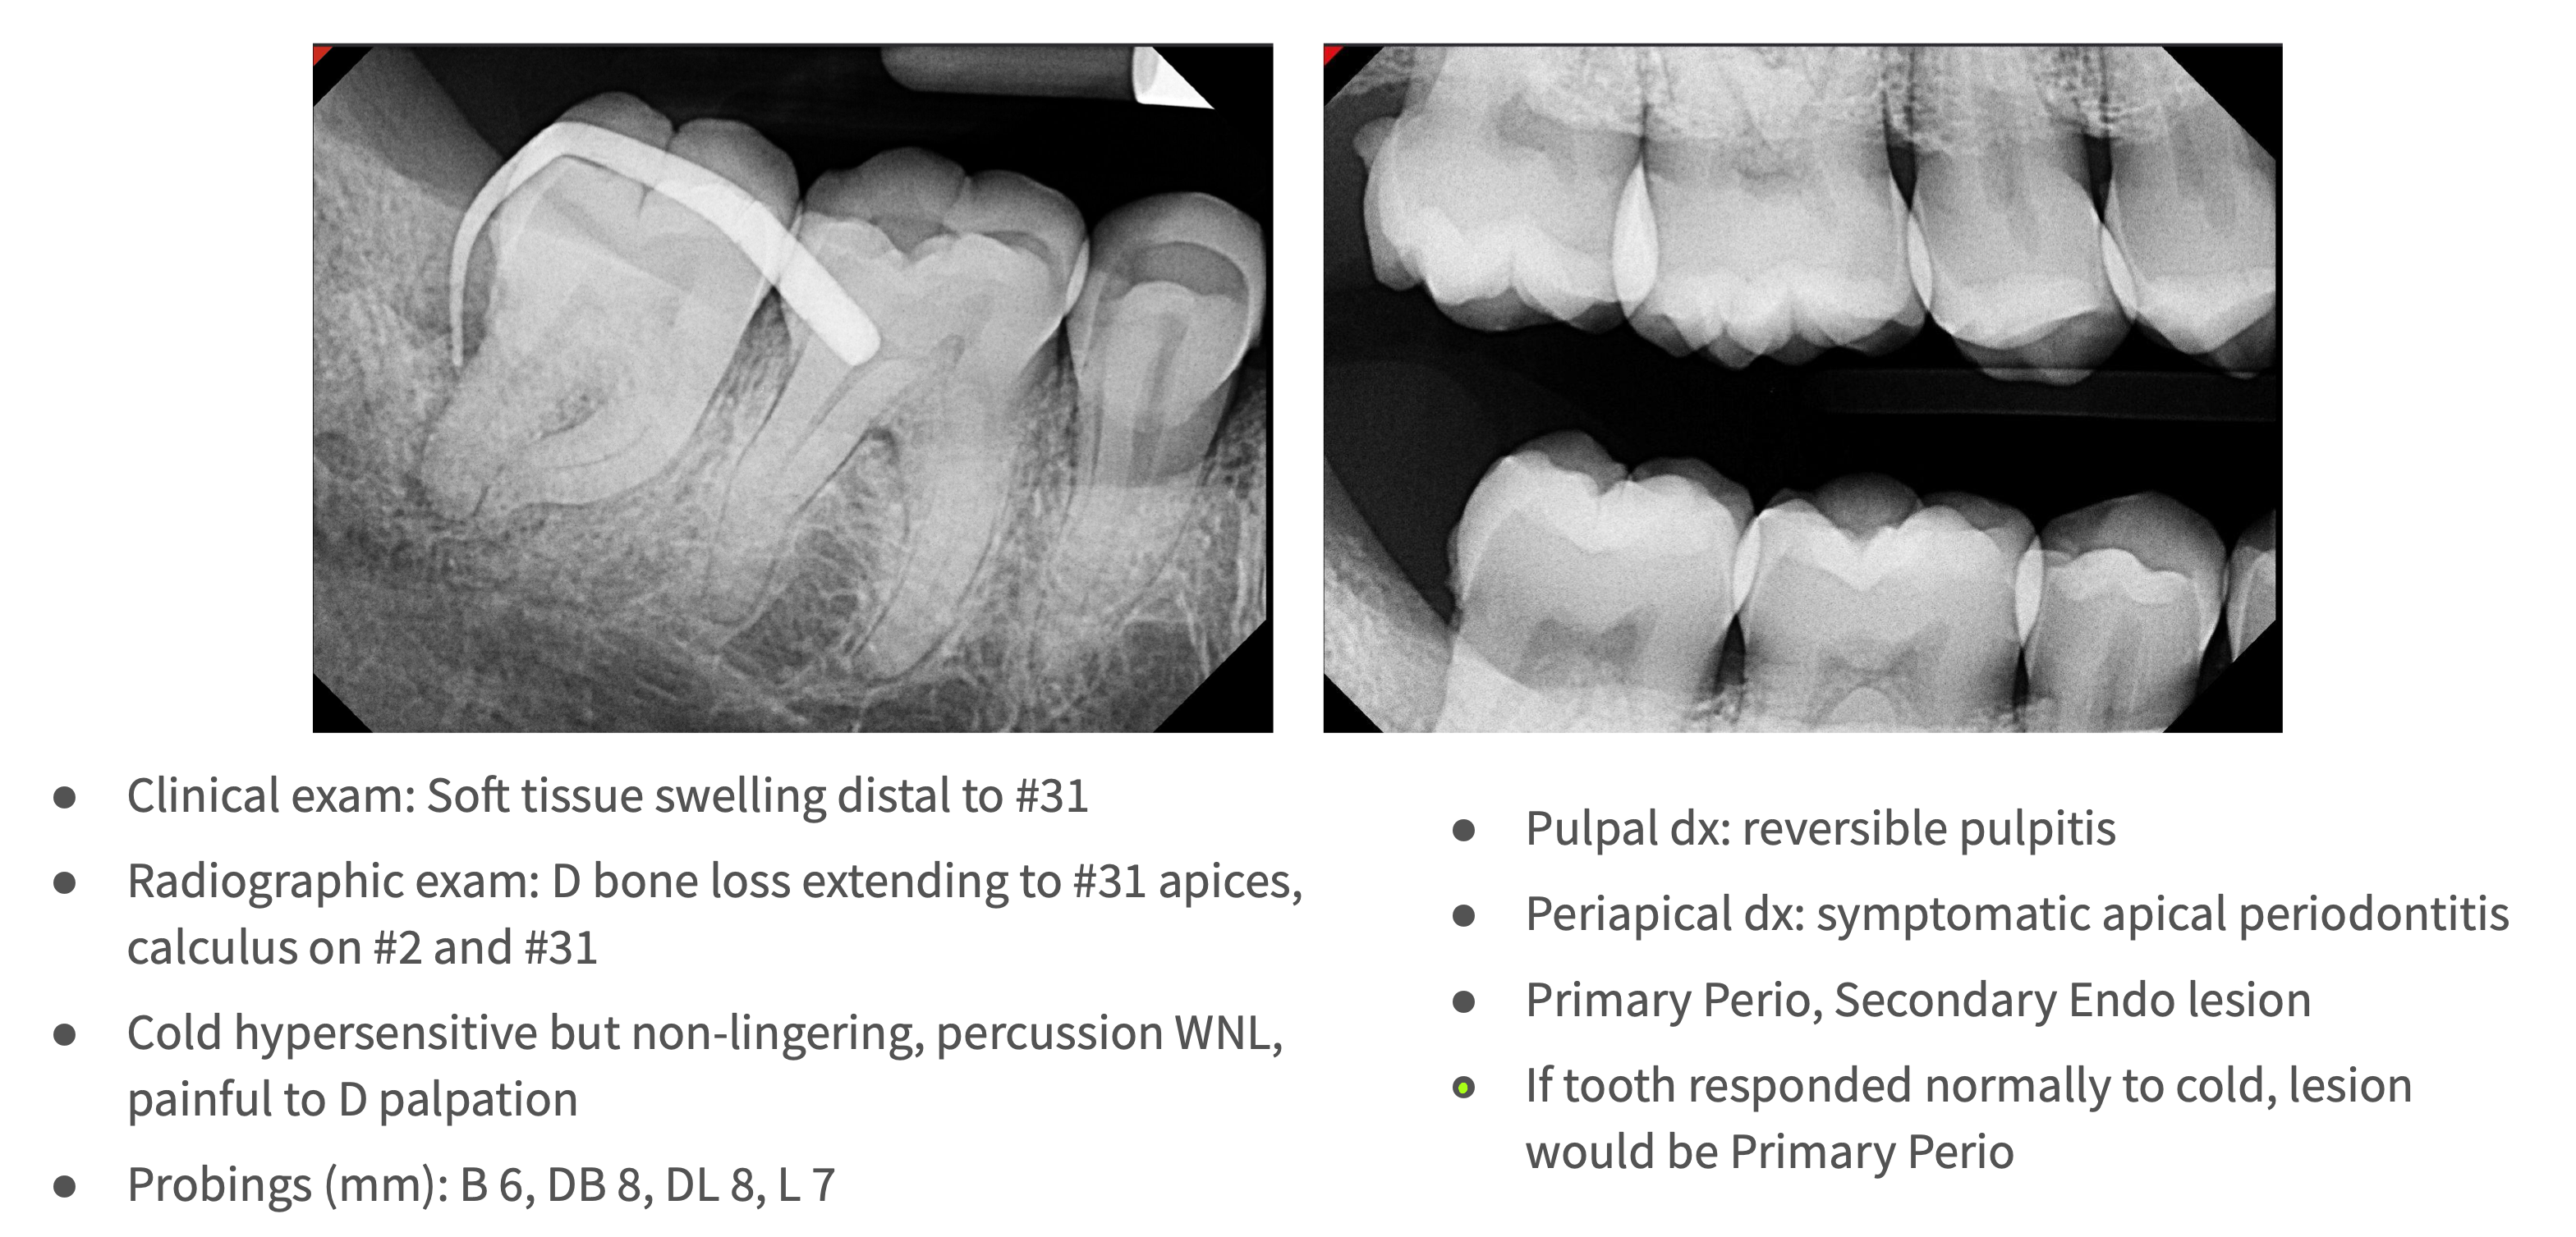

What type of lesion?

Primary perio with secondary endo

What is the pulpal diagnosis for primary perio with secondary endo lesions?

Symptomatic Irreversible Pulpitis (or rarely Necrotic Pulp)

What is the periapical diagnosis for primary perio with secondary endo lesions?

Symptomatic Apical Periodontitis or Asymptomatic Apical Periodontitis